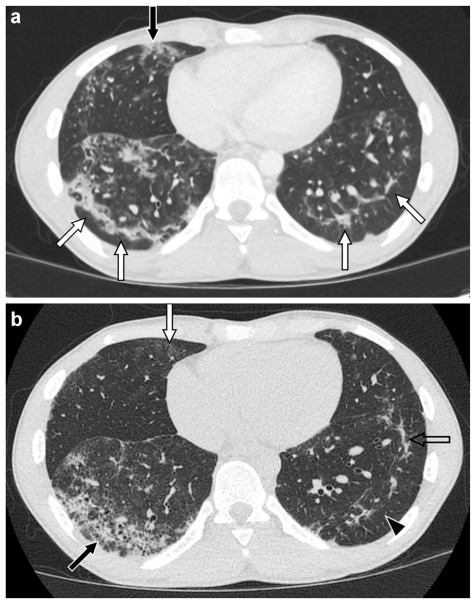

本综述系统阐述了儿童药物性肺病(Medication-induced Lung Disease)的影像学特征、临床诊断与管理策略,强调CT(Computed Tomography)在识别OP(Organizing Pneumonia)、DAD(Diffuse Alveolar Damage)、NSIP(Nonspecific Interstitial Pneumonia)等关键模式中的核心作用,为儿科放射科医生参与多学科诊疗提供实用指南。